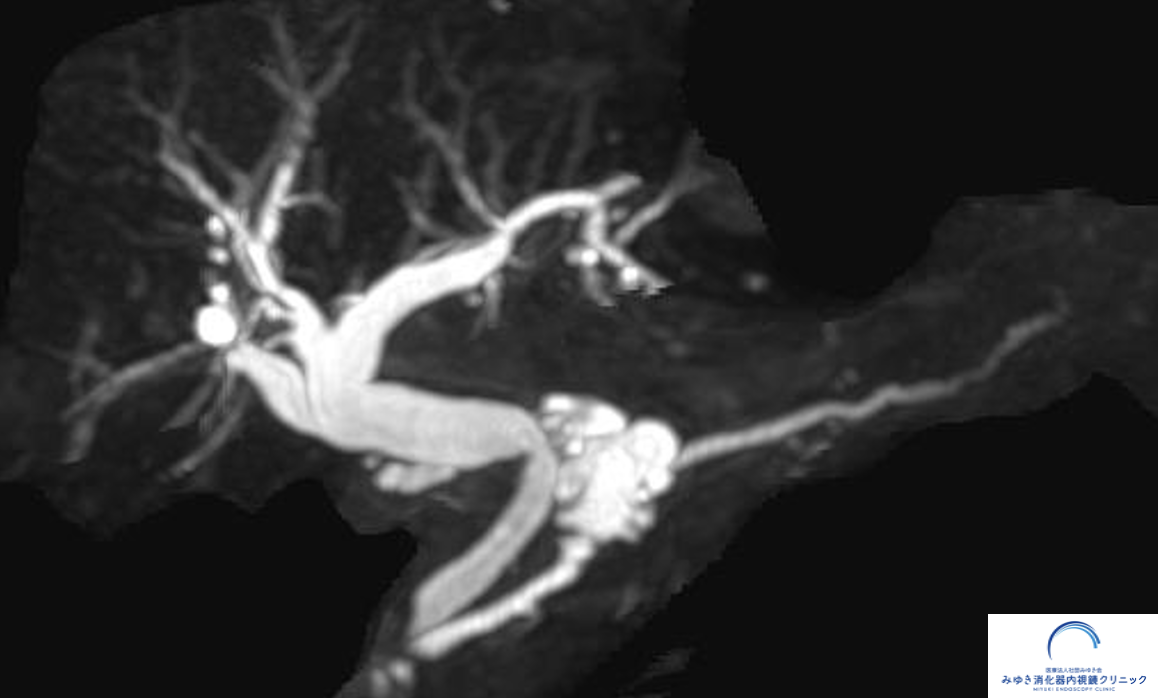

MRI(MRCP)で膵管の枝に嚢胞がみられる分枝型IPMNの例

一般的には、MRIやCTなどの画像検査に加え、必要に応じて超音波内視鏡(EUS)を組み合わせて、嚢胞の変化や膵臓全体の状態を確認していきます。

IPMNの経過観察では、MRIやCTなどの画像検査が基本となります。